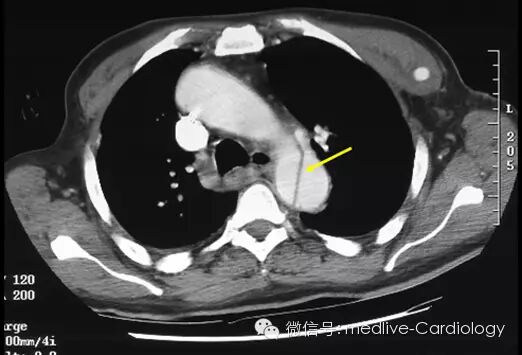

CT扫描是另一种快速而准确的诊断手段,其敏感度和特异度都超过90%。增强CT扫描可以确定夹层扩展范围,观察到将主动脉腔分为两部分的内膜层(黄色箭头),以及识别哪些分支血管血流已中断。采集到的图像还可以到工作站进行三维重建,从而对制定外科手术方案起到辅助作用。后续的检查可以用来观察患者术后情况及评估术后并发症。